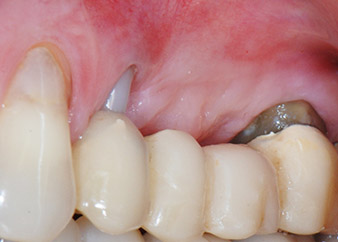

Un mese più tardi, nel giorno programmato per l'intervento, il dolore e l'infiammazione in corrispondenza del dente 24 erano minimi, ma era ancora presente mobilità di classe 2 secondo Miller. Dopo l'apertura dei lembi e la pulizia del tessuto periapicale e periradicolare infetto, l'estensione della mancanza ossea si è resa evidente (Figg. 2 e 3).

Tutto il tessuto osseo vestibolare e distale era mancante in corrispondenza della radice buccale. La possibilità di attacco era essenzialmente ristretta alla radice palatale, evidenziando la prognosi negativa preliminare. Anche il dente 27 mostrava un punto di attacco orizzontale ridotto e una rarefazione apicale minima (cfr. Fig. 1), senza sintomi clinici.

Si è mantenuta , tuttavia, l'idea iniziale di conservare entrambi i denti come appoggi temporanei del ponte durante il periodo di sei mesi per l'osteointegrazione degli impianti. In seguito la situazione si sarebbe assestata. In primo luogo, in un tentativo di risolvere il problema entro-periodontale, la superficie radicolare rimanente è stata attentamente sbrigliata con apparecchiatura piezoelettrica (Piezomed di W&H con l'attacco S1 a spatola, progettato in origine per l'erosione della parete laterale del seno mascellare) Fig. 4).